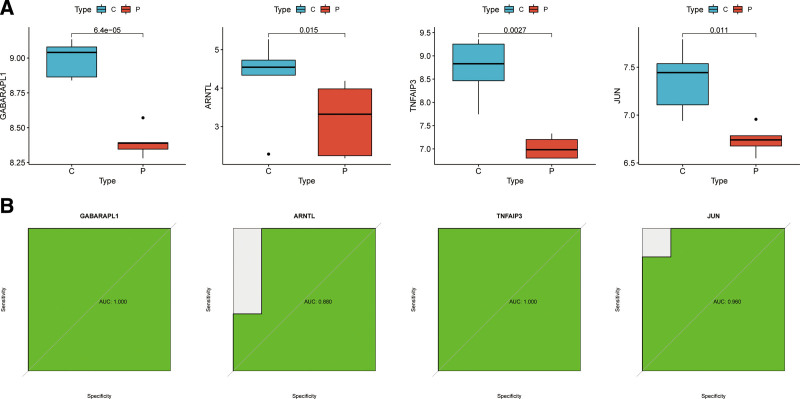

The difference of the expression of the 4 feature genes between OA samples and corresponding normal tissue samples were confirmed again in the validation cohort (GSE1919 dataset). The expression levels of GABARAPL1, TNFAIP3, ARNTL, and JUN in OA samples were lower compared with that in the paired normal tissue samples (Fig. 6A). The results of ROC analysis (Fig. 6B) showed that AUC was 1.000 for GABARAPL1, 0.880 for ARNTL, 1.000 for TNFAIP3, and 0.960 for JUN.